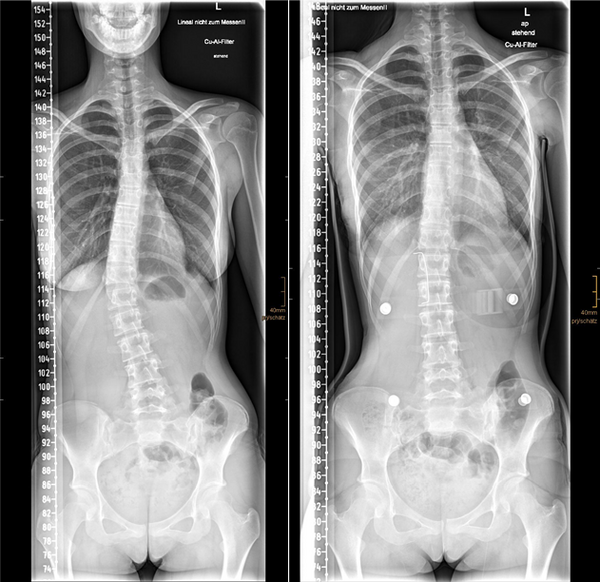

Bei Erwachsenen und ausgewachsenen Jugendlichen ist der Standardeingriff die Spondylodese (Versteifung). Hierbei wird die Wirbelsäule durch Schrauben und Stäbe begradigt und in dieser korrigierten Position knöchern versteift. Moderne Operationstechniken, wie zum Beispiel der Einsatz der intraoperativen Navigation und ständige Überwachung der neuralen Strukturen (Neuromonitoring), machen diesen Eingriff heute sehr sicher und erzielen hervorragende Ergebnisse.

Skoliose_Spondylodese

Bild 2: Ein Beispiel für die operative Behandlung einer Skoliose mit einer Spondylodese (Versteifungsoperation). Die Krümmung wird mit dem Implantat korrigiert und die Wirbelsäule stabilisiert.